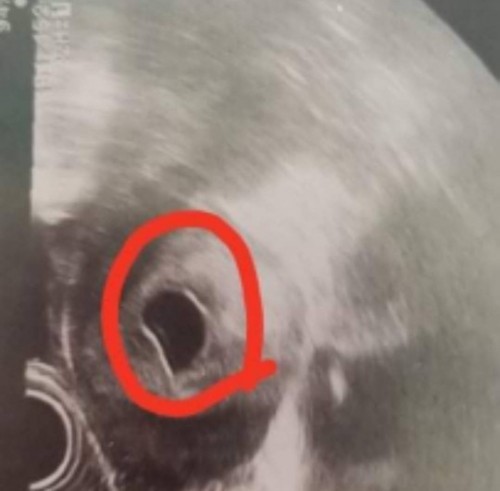

เราท้องได้9weekแต่ไปซาวกับไม่เจอตัวน้องคะซาวทั้งหน้าท้องและทางช่องคลอดตอนนี้เครียดมากการคัดเต้าก็ยังปกติคะมีเหม็นกลิ่นอาหารบ้างตอนนี้จิตตกเข้าออกตามเว็บหาข้อมูลทำใจไม่ได้เลยคะแม่ท่านไหนเป็นแบบนี้บ้างคะ

บ้านนี้ซาวหน้าท้องก้ไม่เจอค่ะ 8week หมอเลยซาวแบบทางช่องคลอด ถึงเห็นเพราะน้องตัวเล็กมาก 😊

ซาวด์ทางช่องคลอด9wคะ มีเสียงหัวใจเต้นคะดีใจมากแต่มีถุงน้ำในรังไข่คุณแม่กังกลมากคะ